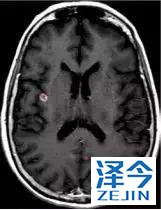

脑转移病变显示缩小了95%!

初始, 2018年6月 3周期 2018年8月